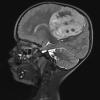

ETMR - Embryonal Tumor Multilayered Rosettes (9)